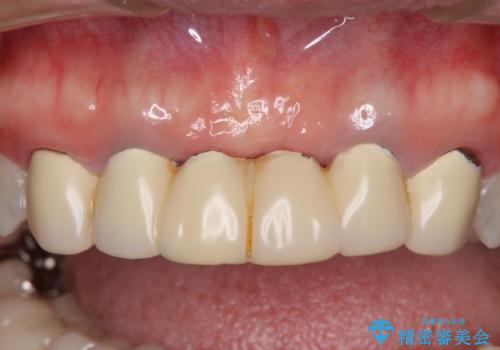

金属を使用した前歯のブリッジや奥歯の銀歯は全てオールセラミッククラウンまたはセラミックインレーとし、左下の奥歯はインプラントにより治療を行うこととしました。

外科処置を行うため、治癒を待つ期間が数ヶ月あるため、その期間を利用して下顎前歯のスペースを矯正治療で閉じることとしました。